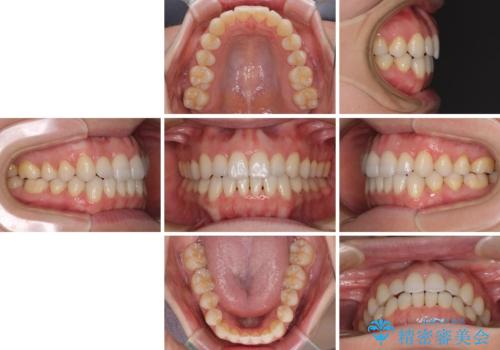

- 1年2ヶ月

オープンバイトは舌の突出癖により誘発され、治療後も突出癖が残っている容易に後戻りしてしまいます。

治療期間を短縮するためにも、舌突出癖の改善が極めて重要となります。